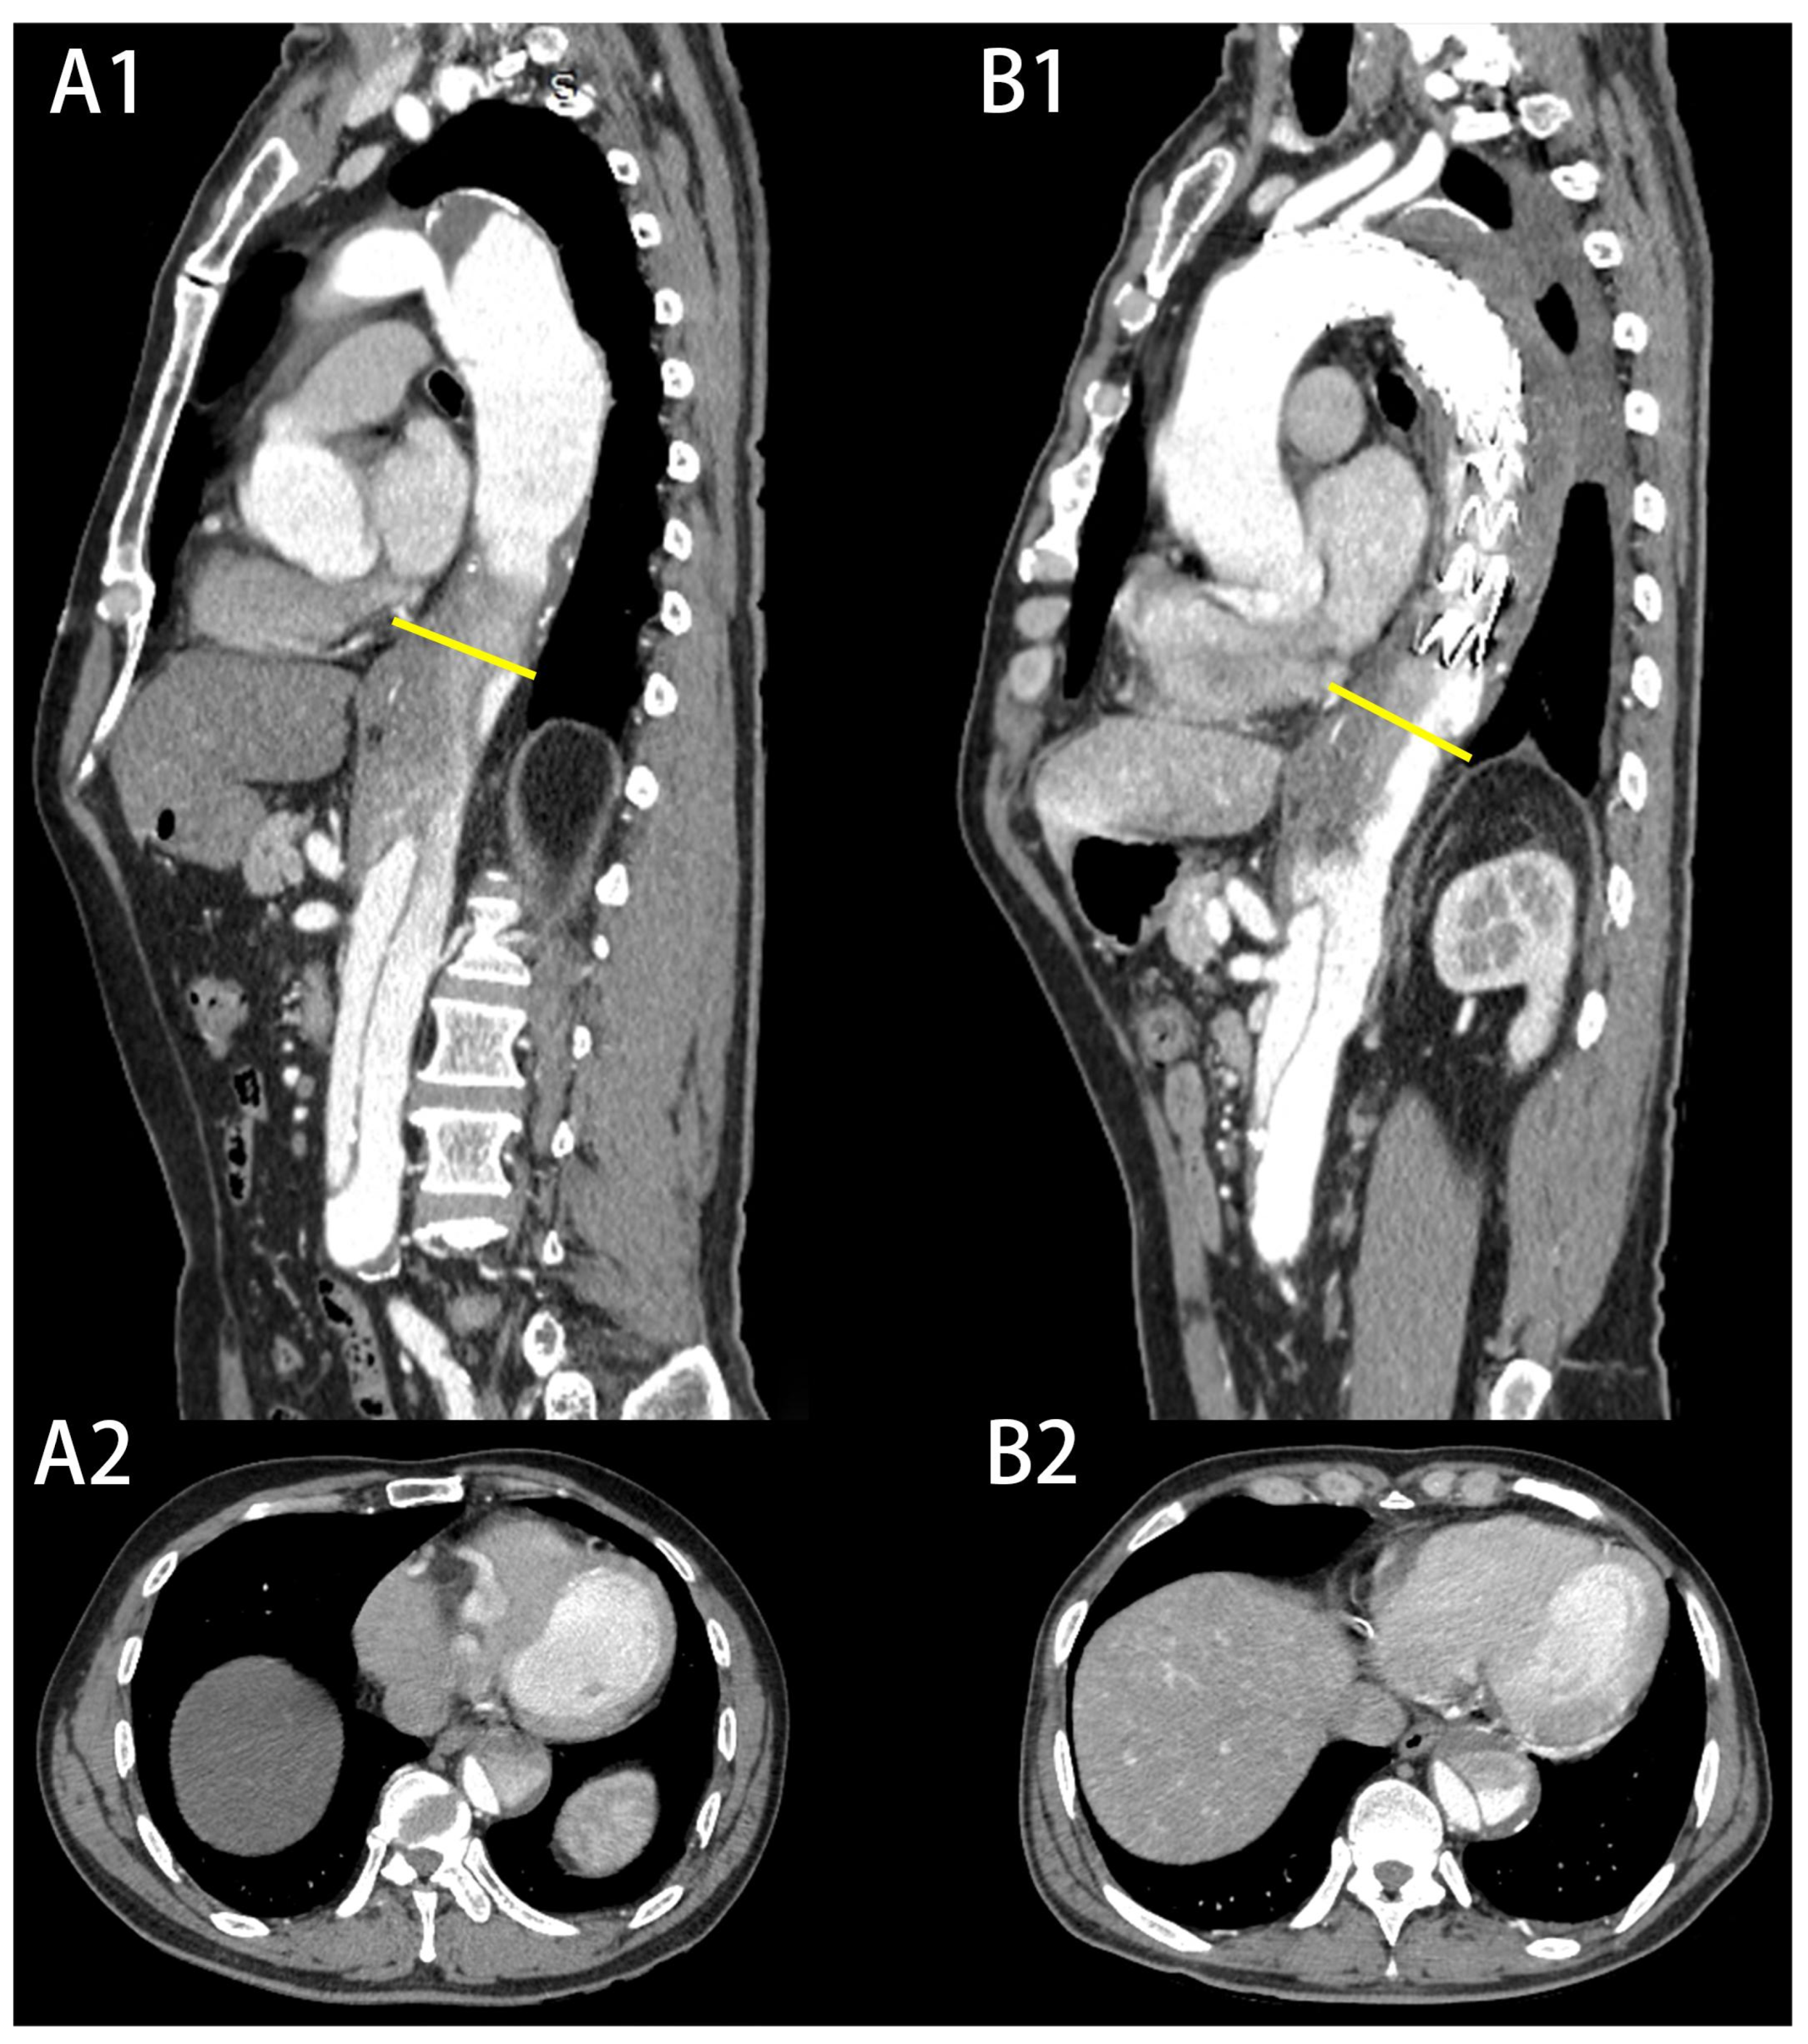

| Partial thrombosis of FL, n (%) | 9 (60.0) | 7 (8.6) | <0.001 |

| Maximum descending aortic diameter (mm), mean ± SD | 41.3 ± 4.5 | 37.5 ± 3.0 | <0.001 |